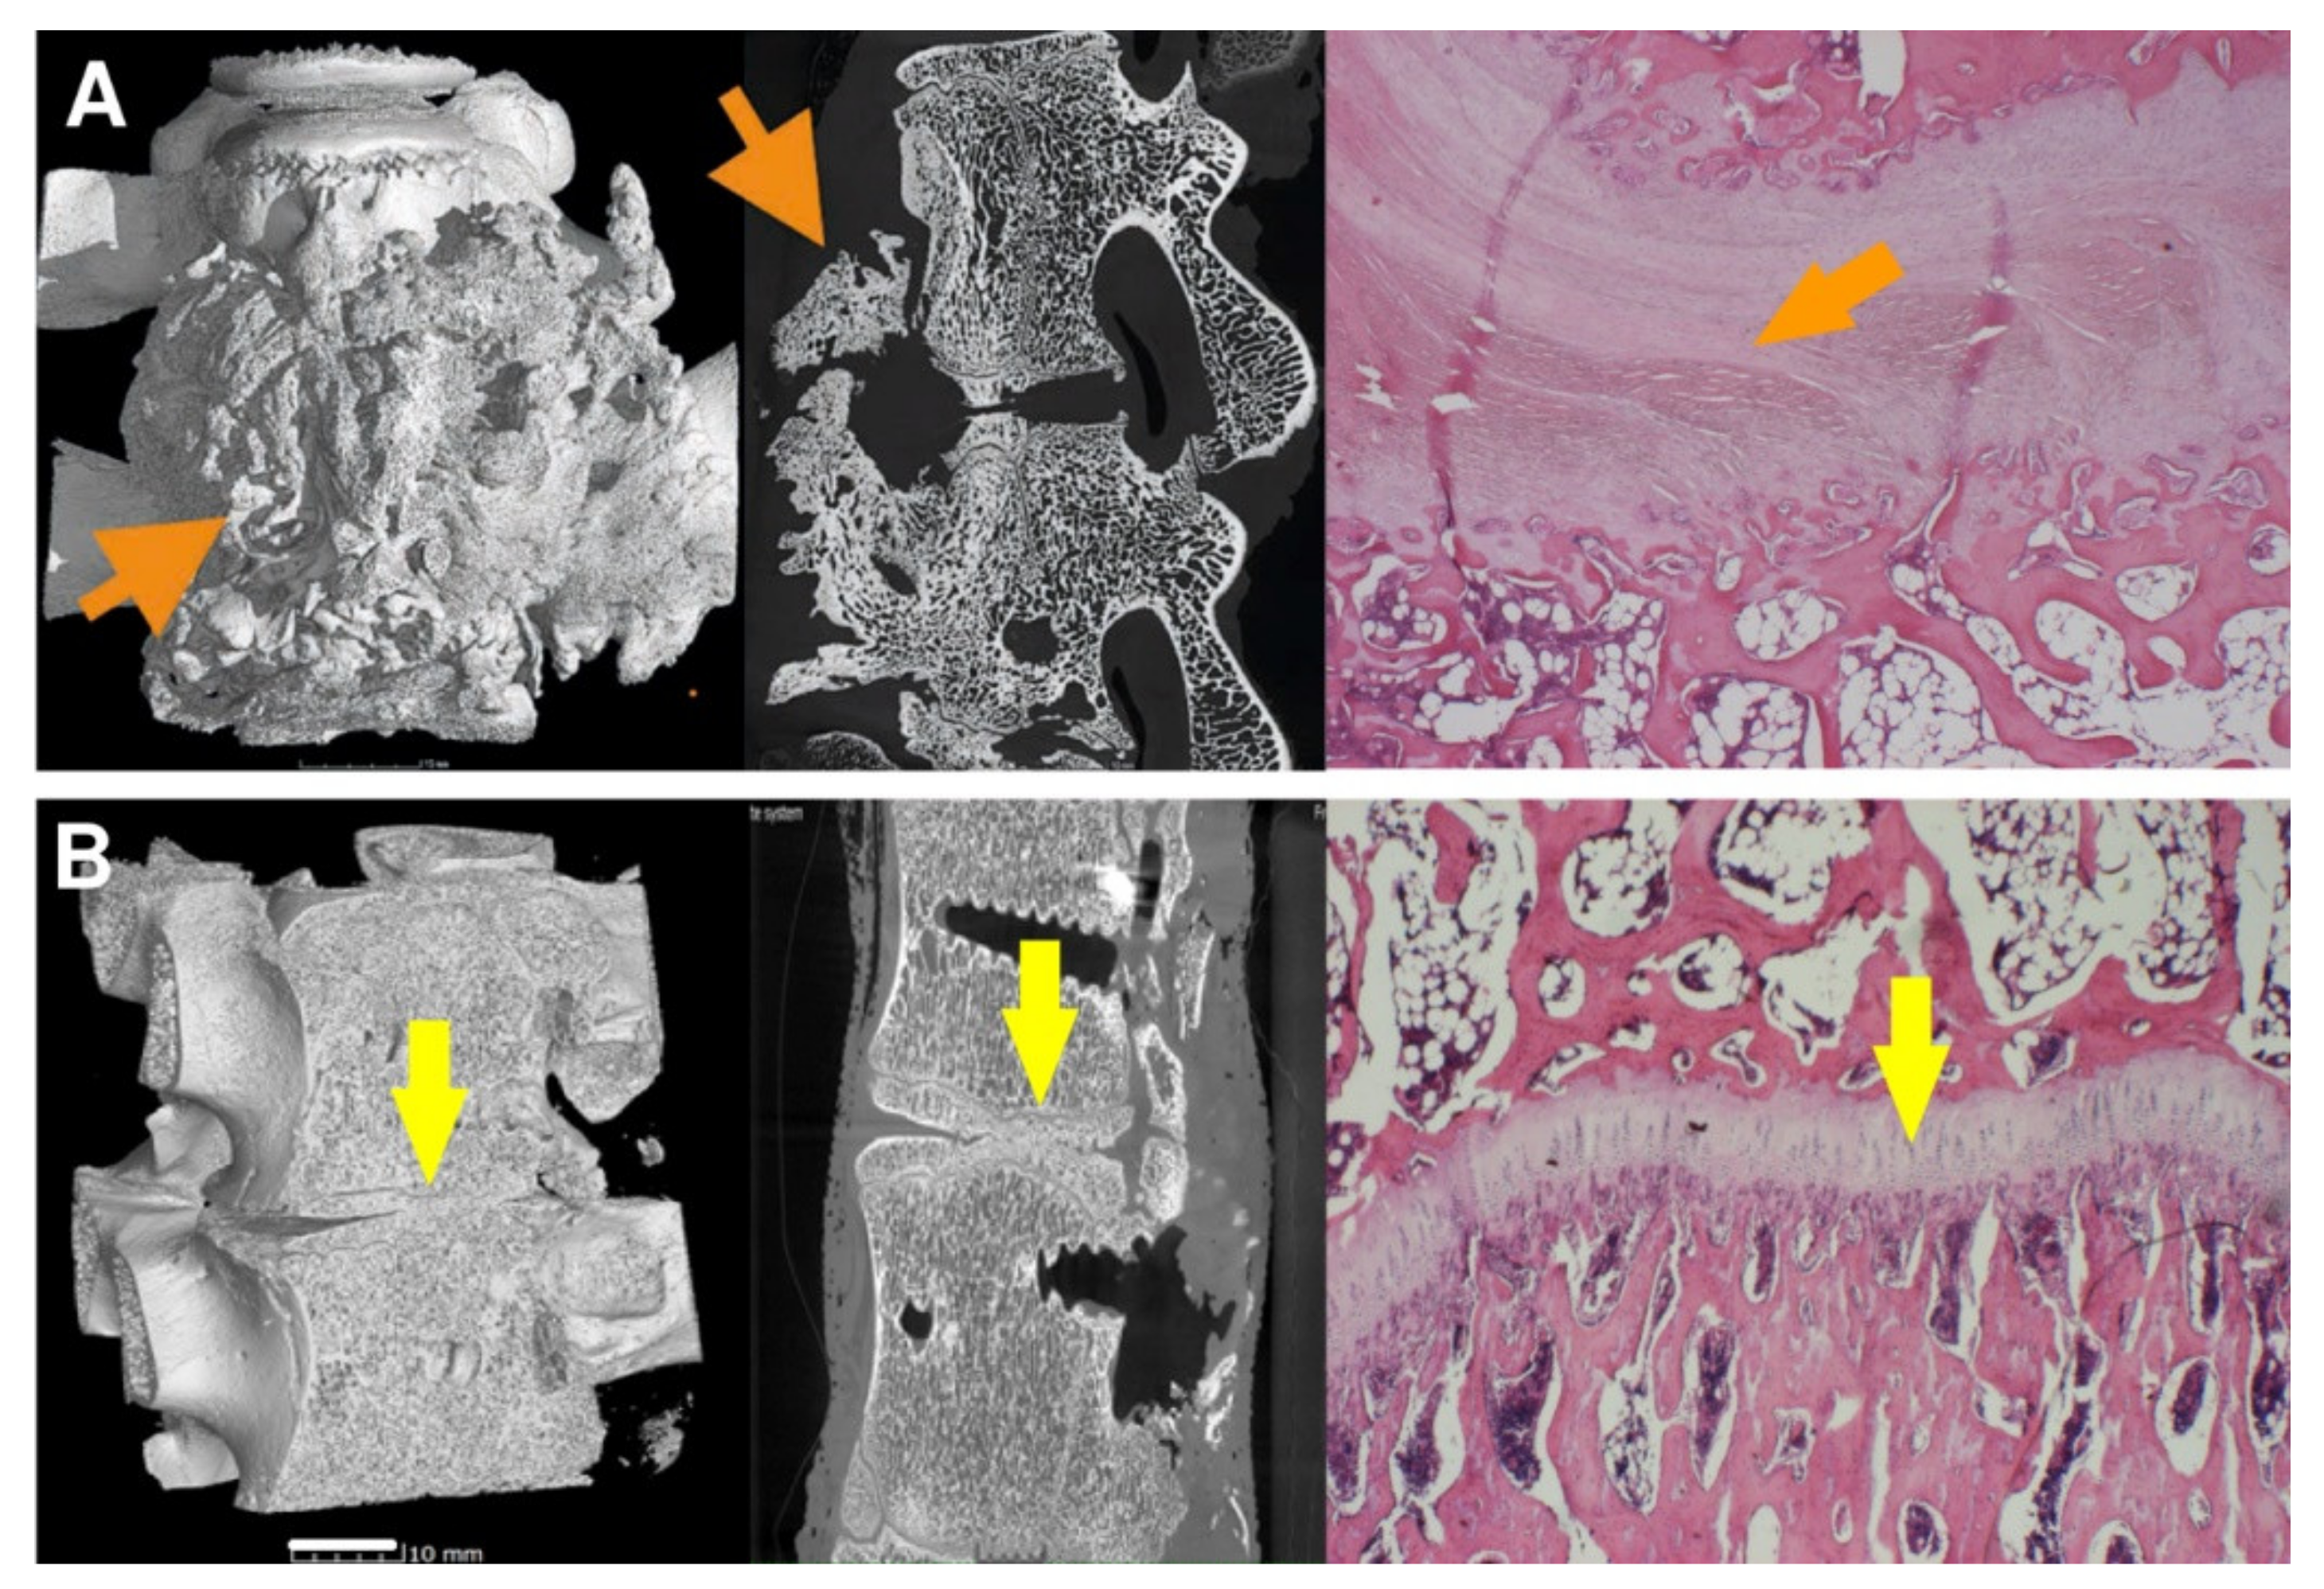

3.4. Micro-CT

3.5. Histology